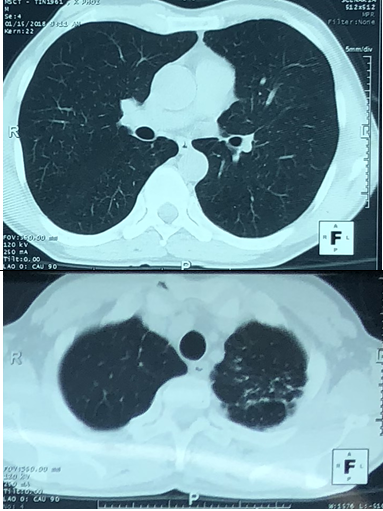

-   Cắt lớp vi tính lồng ngực: U thùy dưới phổi phải kích thước 56x81mm, ngấm thuốc sau tiêm. Khối mờ đỉnh phổi trái kích thước 28mm, nốt mờ nhỏ phân thùy lưỡi phổi trái.

-   Chụp cắt lớp vi tính lồng ngực:

Trước điều trị: U phổi phải kích thước 56x81mm

Sau điều trị: U phổi phải kích thước 35x40mm

Trước điều trị: Khối mờ đỉnh phổi trái kích thước 28mm, nốt mờ thùy dưới phổi trái.

Sau điều trị: Khối mờ đỉnh phổi trái là dải xơ hóa, nốt mờ nhỏ thùy dưới phổi trái không còn.